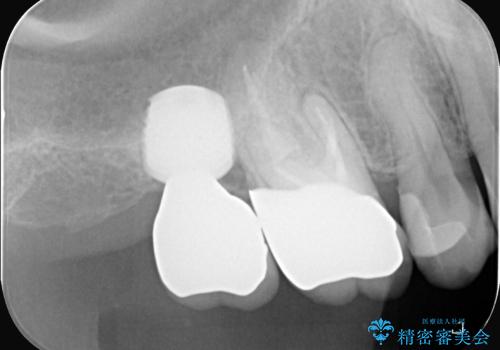

- 治療計画

- 患者様は、右側の奥歯でしっかり噛めないことを主訴に来院されました。診察の結果、右上6・右下6の根管治療が不十分で、感染のリスクがある状態と判断。これらの歯は再根管治療を行い、セラミッククラウンで補綴することにしました。また、右上7・右下7は欠損しており、噛み合わせを回復するためにインプラント治療を計画しました。

まず、右上6・右下6の根管治療を再度行い、根の状態をしっかり整えた上で、セラミッククラウンを装着しました。さらに、欠損していた右上7・右下7にはインプラントを埋入し、セラミッククラウンを装着。治療後は、「奥歯でしっかり噛めるようになり、不安なく食事ができるようになった」と患者様にも大変ご満足いただきました。